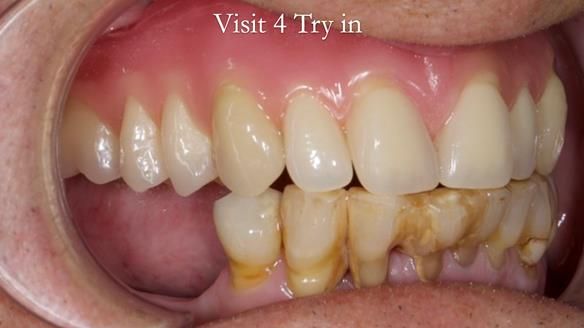

Welcome to my Newsletter 54 showing the making and fitting of dentures (a complete upper metal reinforced denture, a lower immediate partial denture and a definitive Scandinavian designed, metal based lower partial denture) for David, a 75 -year-old man. The full protocol workflow is presented including the use of dentate photographs to mimic his natural teeth.

The clinical situation and treatment process is shown in detail below. I provided the clinical work. Rowan Garstang, my dental technician, provided the technical work.

Interestingly we found that the upper complete denture when finished and fitted didn’t have good enough retention for David’s satisfaction. It was relined by adding compound to the buccal flanges – to almost overextend into the sulcus to ‘create’ a sulcus, followed by using a light bodied silicone impression material. This improved the function of the C/-considerably. A lower Scandinavian hygienically designed lower RPD was also provided which helped with occlusal stability and reseating the upper denture – further improving the fit.